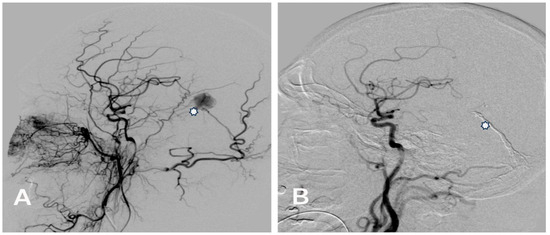

Complete occlusion of the DAVF with Menox™ and other agents was evident in 68.4% (n = 13/19) of patients. Complete occlusion (100%) was observed in the sinus rectus, transverse sinus, and diploic veins of the orbital roof, while complete occlusion was noted in the falcotentorial sinus in 50% of patients (Figure 1 and Figure 2) and in the superior sagittal sinus in 60% of patients.

Hemorrhagic manifestations are one of the most critical issues in managing DAVFs due to the increased risk of rupture, particularly in higher-grade lesions. Therefore, classifying DAVF is essential for treatment planning and prognostication. Two commonly used classification systems, the Cognard and Borden classifications, are invaluable tools in this regard. In our study population, the Cognard classification system revealed a predominance of type IV DAVF (Figure 1 and Figure 2), characterized by retrograde leptomeningeal venous drainage with venous ectasia (Table 1). In patients with type IV DAVF, the most common symptoms were headache, nausea and vomiting, and neurologic conditions such as seizure and disorientation due to cerebral venous hypertension, which in our study was neuroradiologically manifested by bilateral thalamic edema in one patient (Figure 2). Classification helps tailor the treatment strategy to the specific characteristics of the lesion.

Figure 1. (A) Pre-embolization lateral angiogram of a Cognard type IV falcotentorial DAVF with venous ectasia (asterisk) presented with right-sided intracerebral hemorrhage treated with Menox 18 through the middle meningeal artery. (B) Control post-embolization angiogram of the right common carotid artery showing the complete occlusion of the DAVF and the cast of Menox 18™ (asterisk).